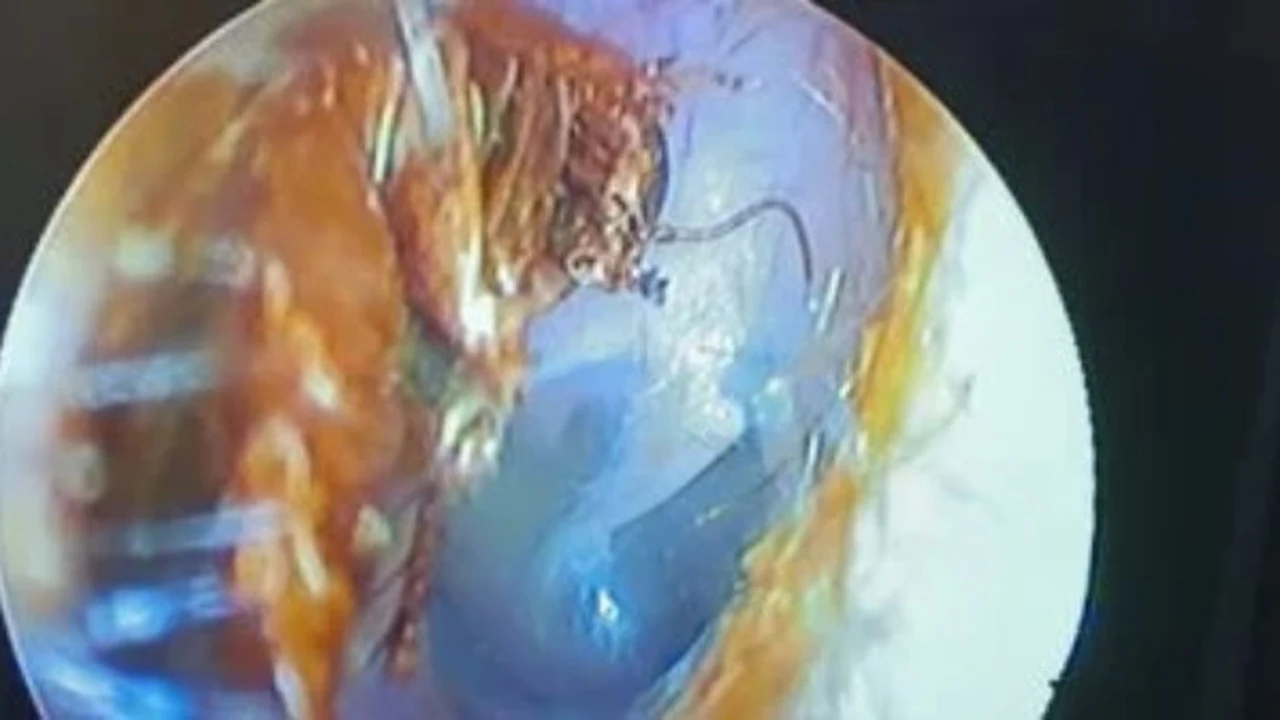

في واقعة طبية نادرة شهدتها محافظة القليوبية تمكن فريق طبي من إنقاذ شاب عانى من آلام مبرحة على مدار يومين متواصلين ليكتشف الأطباء بعد الفحص الدقيق وجود حشرة صرصور حية داخل أذنه ما استدعى تدخلا جراحيا عاجلا لاستخراجها وتفادي حدوث مضاعفات خطيرة.

تعود تفاصيل الحادثة إلى جلوس الشاب في أحد المقاهي حين تسلل الصرصور إلى أذنه فجأة مسببا له التهابا وألما حادا لم يتوقف مما دفعه للتوجه إلى المستشفى بحثا عن علاج لمعاناته المستمرة وبعد إجراء الفحص اللازم تبين وجود الحشرة ليتم استخراجها على الفور.